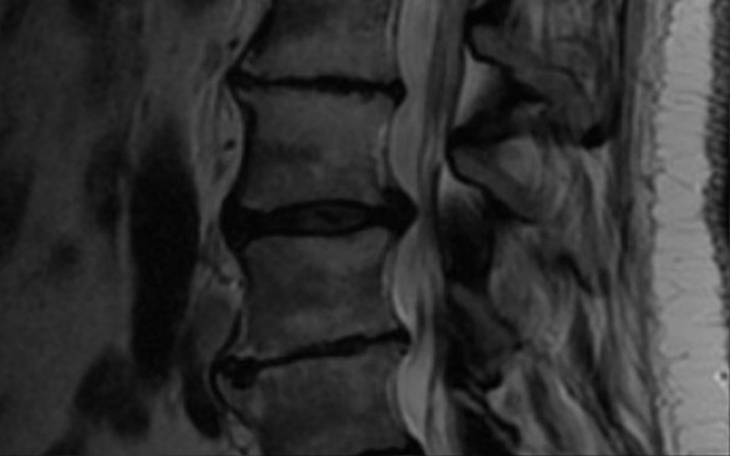

Witam. Jestem młoda mamą 3 dzieciaczkow. A by za nimi jeszcze nadążyć musicie mi pomóc. A więc powiem krótko, mój kręgosłup jest coraz krótszy co idzie za sprawą znikajacych Zelów miedzykrazkowych. W wieku 28 lat neurochirurg uznał że mój kręgosłup odpowiada 50 letniemu kregoslupowi, aż boję się co będzie za parę lat, a BOJĘ SIĘ BARDZO. JAK NIGDY ! Dlatego potrzebuję kosztownej operacji by mój kręgosłup jeszcze ZYŁ gdy będą mnie potrzebowały dzieci w przyszłości.